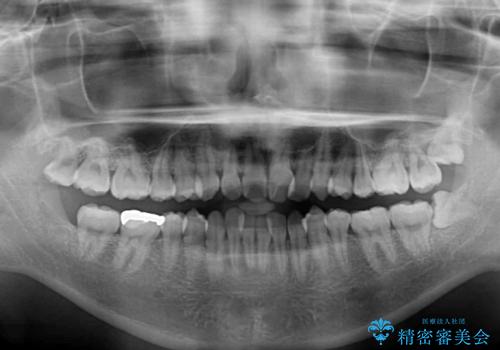

- 上下前歯の叢生を気にして来院された患者様です。

当初はインビザラインにて治療を開始しましたが、自己管理による治療が難しくなり、ワイヤー矯正へ転換して継続しました。

2年ほどインビザライン矯正を続けましたが、終了することができず、ワイヤーへ転換後は1年弱で終えることができました。